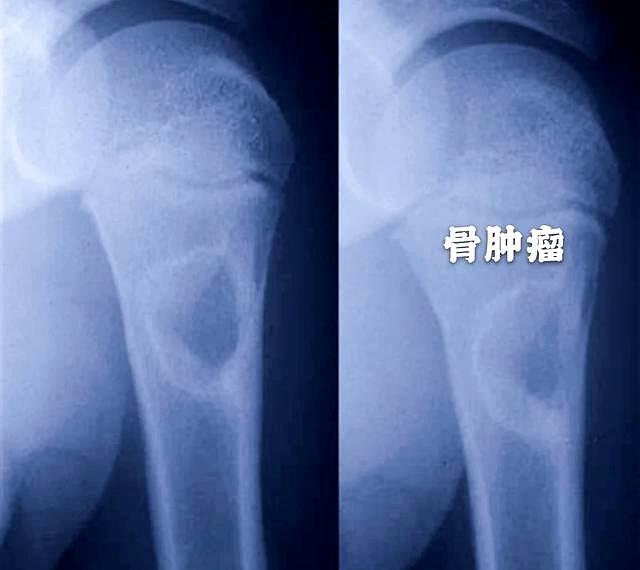

如果肩痛的时间不是特别长,而且症状也不是特别重,在就诊的时候做普通的肩关节x线片子就可以了,我们主要通过肩关节的x线片子可以看看是否有明显的肩关节撞击,是否有肩关节的骨关节炎,肩关节的关节间隙是否有了明显的狭窄,另外现在的x线清晰度是非常高的,如果存在着可疑的、比较大的骨肿瘤,通过x线也能稍微看出些端倪。虽然并不能确诊但是可以帮助我们做筛查

很多人觉得肩关节疼痛就是肩周炎,觉得拍片子是浪费钱或者是没有意义,其实不然,有筛查的意义在这里面,谢医生曾经遇到过一个肩痛的患者,肩关节活动范围非常正常,但是拍片发现他的肩关节是一个巨大的骨肿瘤,医疗没小事,谨慎点不为过

图片

●如果肩痛的时间比较久了,而且经过治疗效果不好,同时还存在着消瘦、无力等症状,建议要进一步的详细检查。最起码要给肩痛的患者进行肺部ct的检查,一定要排除是否存在肺癌,尤其是肺上沟癌。进行肩关节的核磁检查,也是可以明确是否存在肩关节局部肿瘤的,在核磁影像上可以非常好的判断肩关节的结构是否存在问题,同时是否存在软组织的改变以及是否存在肿瘤。